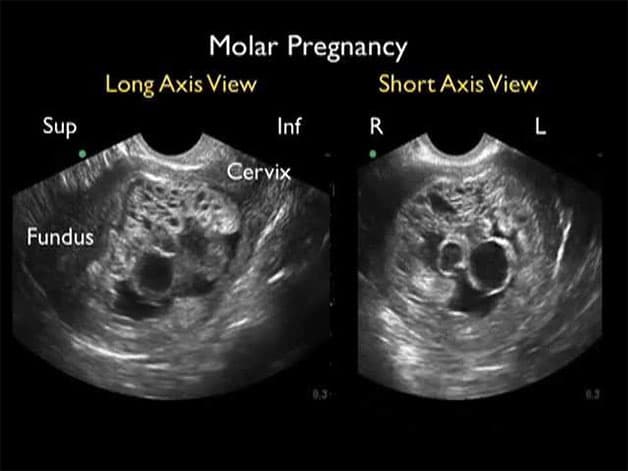

– Siêu âm không nghe được tim thai, không thấy phôi thai.

– Nếu bạn có bất kỳ các biểu hiện thai trứng kể trên thì nên đến các bệnh viện, phòng khám uy tín để chẩn đoán chính xác tình trạng của mình thông qua việc làm các xét nghiệm và kĩ thuật hình ảnh như siêu âm ổ bụng, xét nghiệm HCG…

Chẩn đoán thai trứng thông qua hình ảnh siêu âm bụng.